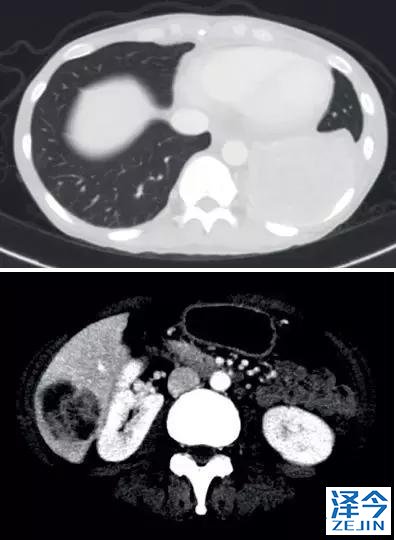

一位77岁的女性患有EPS15-NTRK1 IV期非小细胞肺癌,我们可以看到她的双肺满是病灶,并且出现了肝脏和脑转移,可以说是非常非常晚期了,

既往有乳腺癌史;

既往症状有厌食,乏力,咳嗽,高脂血症;

ECOG 1;

没有接受手术,放疗或化疗。

开始使用larotrectinib 100 mg BID并持续治疗,

第3周期开始:

肺靶病变达到缓解,我们可以明显的看到前后的图像,病灶明显缩小了,

脑转移病变显示缩小了95%!

初始, 2018年6月 3周期 2018年8月